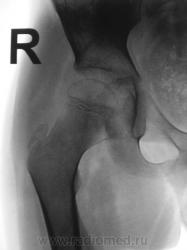

Пациент направлен на конрольное рентгенологическое исследование средней трети бедренной кости с целью оценки консолидации. Ранее - первичный снимок пациент был направлен на рентгенографию средней трети бедра, что и было сделано. Но, при производстве "контроля" рентгенолаборанты захватили тазобедренный сустав в прямой проекции, и возникли неясные сомнения по поводу головки, да и вообще...

Какой-то «змей 2х-головый» и впадина не слава богу. Надо или детских рентгенологов ждать или вторую проекцию делать.

Сама головка не нравится, особенно её нижне-медиальный отдел.

Согласна, что-то и меня в глазах головка бедра двоиться.

Пожалейте ребенка, не надо томографировать. Все укладывается в норму. Просто головка еще маленькая, а медиально - это шеечная шпора. Уж если не верите, снимите оба сустава одновременно.

Вероятно остеопороз головки от функционального щажения, разрушений не видно, капсула (мягкие ткани) параартикулярно - в норме...

А в нижней половине вертлужной впадины всё ОК?

Согласен с теми коллегами которым, в нижнем квадранте вертлужной впадины видится фрагмент головки бедренной кости.В принципе тоже против "линейки", но "змея " добить надо.Почему бы не выполнить ультрасонографию сустава?

Интересная дискуссия. Жаль с опозданием увидел (однако же, много времени уходит, пока всё на сайте просмотришь). На мой взгляд, патологии головки нет, без фрагментации, проекционно пересекается с тенью обызвествляемого Y-хряща. Под головкой медиально, несомненно, есть остеопороз, придающий нечеткость картине. Впрочем, регионарный остеопороз имеет место вследствие закономерной атрофии после иммобилизации. Сюда же наслаивается субстрат т.н. фигуры серпа, еще не оформленный. Впадина нормальная. Кость срослась - замечательно, всем бы такие результаты. Реабилитация обязательна.

Из-за выраженного остеопороза бедра и тазовых костей, некоторые контуры теряются… да ещё кисты в шейке и головке мерещатся. Томограмма сама просится. Вот разве что Ola-la на обмен согласна.